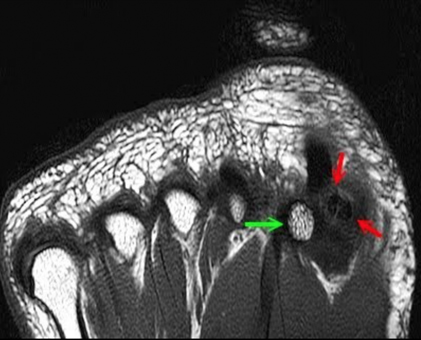

MRI of AVN of the Sesamoid

The Sesamoid should be a white color similar to the other bones (green

arrow)

The sesamoid that is darker is damaged and can lead to AVN (red arrows)

The sesamoid is darker indicating lack of blood flow to the bone.